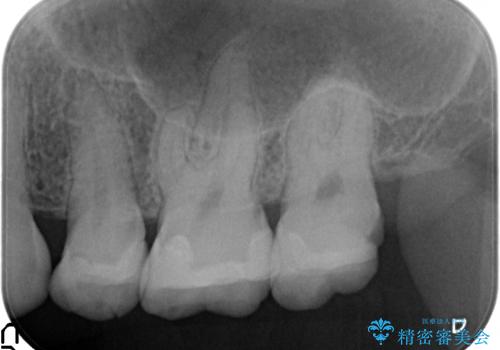

- 左上7が欠けてしまったので診て欲しいといらっしゃった方の症例です。

虫歯を除去後、オールセラミッククラウンによる補綴を行いました。

虫歯治療は虫歯の進行度によって処置が変わってきます。

虫歯が小さければ、インレー・クラウン等による修復・補綴処置を行うだけで済みます。

しかし虫歯が大きくなると神経処置や抜歯等をしなければならない場合もあります。

ですので虫歯治療においては早期発見・早期治療が肝要です。